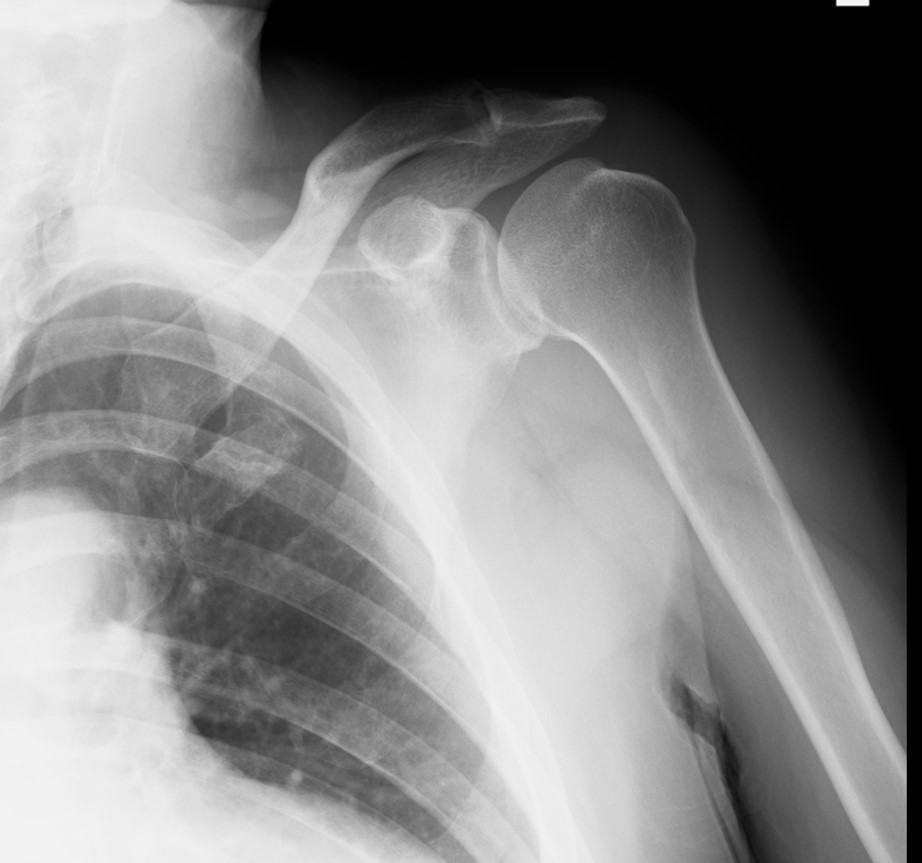

照片3 左肩關節脫位整復後的X光照片